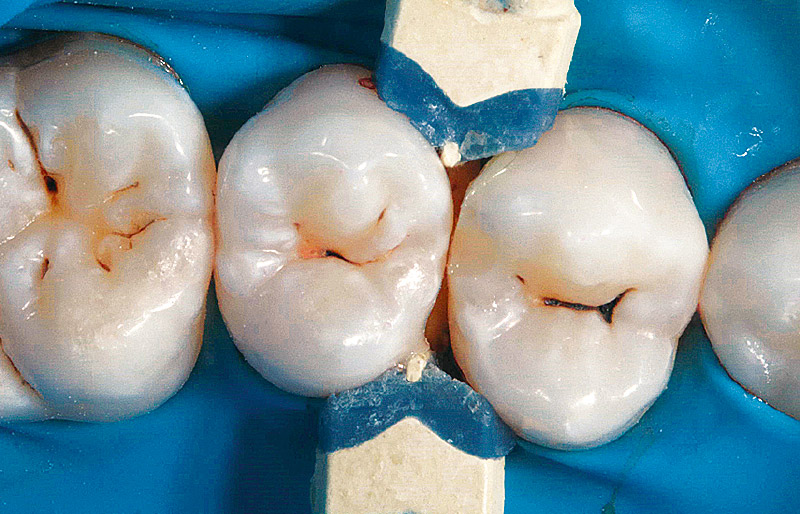

症例1-1 40代女性。術前の状態。1年前から4の遠心にう蝕を確認し、経過観察を行ってきた。![[写真] 透照診では既に4の遠心う蝕が認められていた](/academic/dentalmagazine/wp-content/uploads/sites/2/2024/06/189-7_photo01-2.jpg)

症例1-2 透照診では既に4の遠心う蝕が認められていた。![[写真] 隣在歯を保護しながら拡大視野下でう蝕除去を行う](/academic/dentalmagazine/wp-content/uploads/sites/2/2024/06/189-7_photo01-3.jpg)

症例1-3 隣在歯を保護しながら拡大視野下でう蝕除去を行う。![[写真] ギャリソンデンタル社のマトリックスシステムを使用し隔壁を設置した](/academic/dentalmagazine/wp-content/uploads/sites/2/2024/06/189-7_photo01-4.jpg)

症例1-4 ギャリソンデンタル社のマトリックスシステムを使用し隔壁を設置した。![[写真] 「クリアフィル マジェスティ ESフロー」(クラレノリタケデンタル)を用いて充填を行った。](/academic/dentalmagazine/wp-content/uploads/sites/2/2024/06/189-7_photo01-5.jpg)